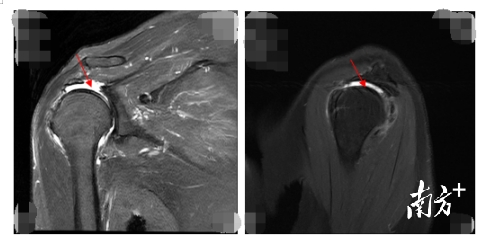

△术前MRI可见冈上肌完全断裂不可修复。

“肩袖由四条肌腱组成,分别为肩胛下肌、冈上肌、冈下肌、小圆肌,李阿姨的冈上肌和肩胛下肌从骨面上撕裂,并出现冈上肌完全吸收萎缩。”他解释道。